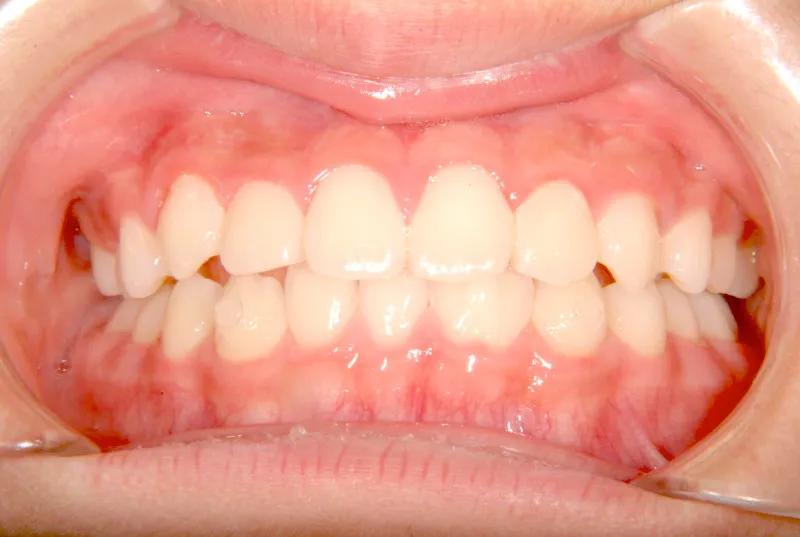

オリジナルの着け外しのできる装置で治療しました。

治療回数○回、4年7ヶ月の治療期間で矯正治療を終了しました。

1期治療で十分な結果が得られたと思います。

治療終了後